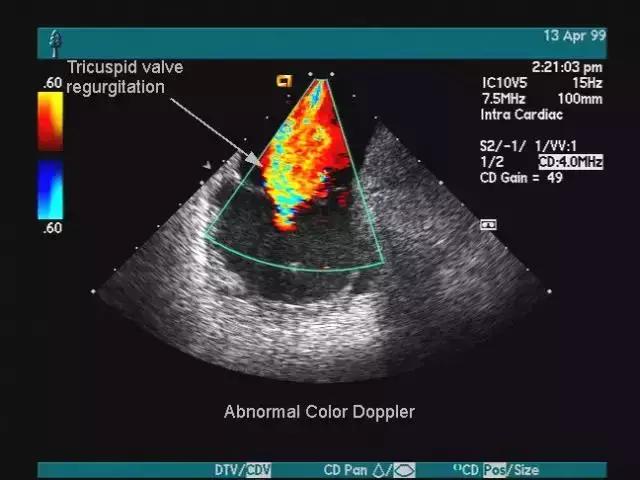

其实彩超就是在黑白B超的基础上增加了一个多普勒信号接收功能。

医生可以在显示器上观测到的图像以红蓝两色为主,面向探头的呈现红色,反之为蓝色。

这种技术能够观测到器官内部血液流动情况,而血流与疾病的性质有密切关系。

在乳腺超声中,血流信号确实与肿块性质相关,往往恶性肿瘤需要大量血液供应,所以其周围血流信号丰富。

一句话,打开多普勒功能医生可以看到红蓝色的血流情况,而关上它,就是普通的黑白B超。

所以大家别再以为彩超就是彩色电视机一样,能看到彩色的脏器,彩超也仅仅只有红蓝两色而已。